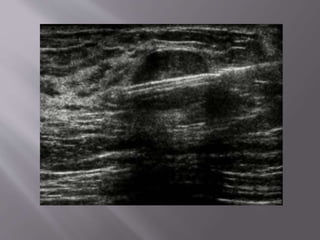

The lump (arrow) in this

patient’s right breast was

thought to be a cyst, but some

Using ultrasound guidance, a fine

needle (white line) is placed so

that its tip (double arrow) is in the

center of the lump (single arrow).

Aspiration is applied by using a

syringe attached to the needle. If

this is a cyst, fluid is drawn into

the syringe as the lesion collapses.

The lump (arrow)in this patient’s right breast was thought to be a cyst, but some features are not characteristic and aspiration was necessary.

Using ultrasound guidance,a fine needle (white line) is placed so that its tip (double arrow) is in the center of the lump (single arrow). Aspiration is applied by using a syringe attached to the needle. If this is a cyst, fluid is drawn into the syringe as the lesion collapses.